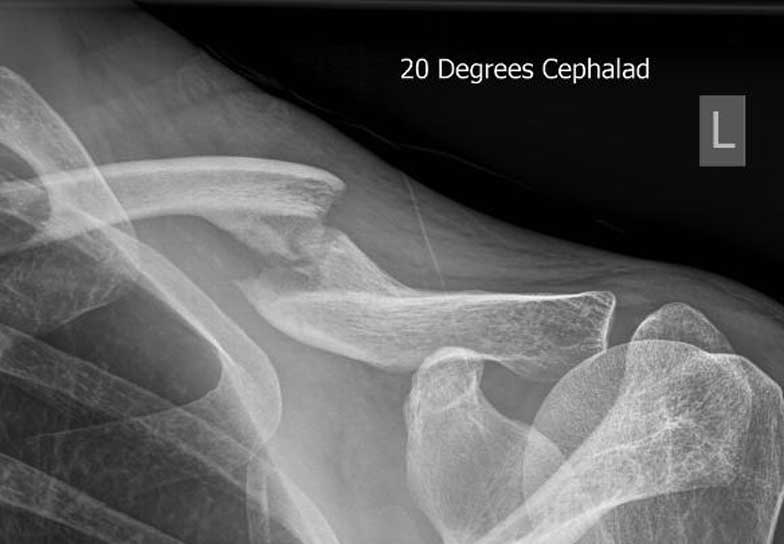

This lady is 65 years old and fractured her clavicle 28 years previously in a motor vehicle accident. At that time she was told that nothing could be done for her. It never really healed and as a result she had ongoing pain in her scapula, shoulder and clavicle. I managed to fix her fracture with a plate and screws and kept her in a sling longer than I normally would and reviewed her for a longer period of time than normal but at her final visit eleven months after her surgery she was delighted with the result as she had no pain, a full range of motion, the fracture was solidly healed and she was doing everything she wanted to do.

Malunion fracture before surgery

Malunion fracture after surgery

Move the slider to compare before surgery and 11 months after surgery